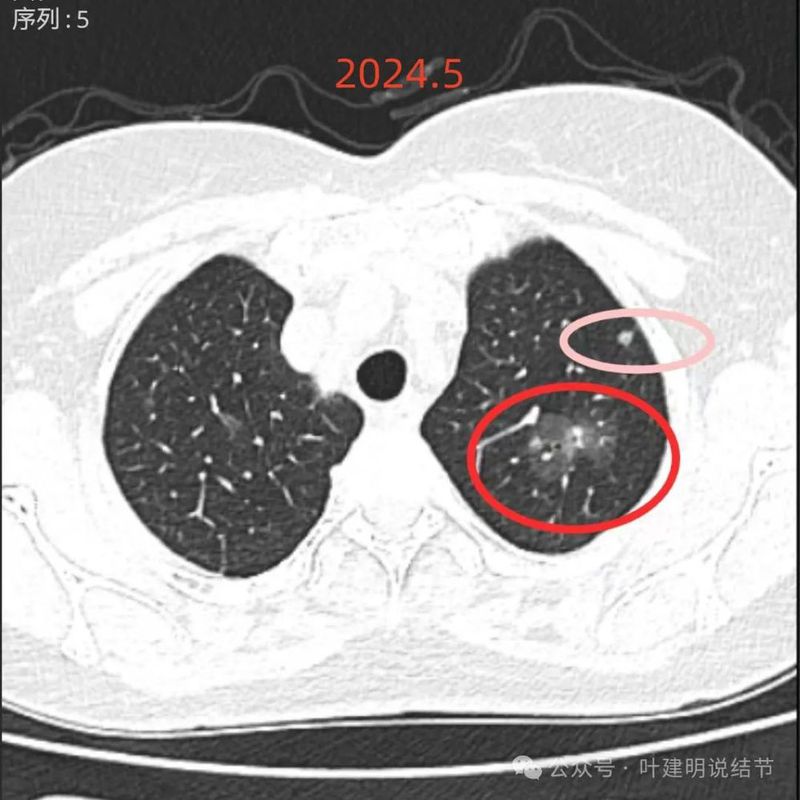

再看2024年5月时的影像:

病灶1:左上叶胸膜下磨玻璃结节,密度偏高但没到实性,轮廓与边界清,考虑原位癌可能性较大;

病灶2:左上混合密度病灶,较前有明显增大,密度也有增高,灶内实性成分较前明显,表面分叶。考虑浸润性腺癌可能性大些。

病灶5:左上叶磨玻璃结节,有血管贴边以及小分支进入病灶内,边缘有毛刺样征,整体轮廓较清,考虑原位癌或微浸润性腺癌可能性较大;

两肺多发磨玻璃结节,部分是混合密度。主病灶是红色这处在左上叶的,对比2021年有明显增大进展,考虑是浸润性腺癌可能性大,或者微浸润性腺癌;粉色的考虑原位癌可能性大;橘色的考虑不典型增生可能性大;黄色的考虑肺泡上皮增生可能性大;紫色的考虑微浸润性腺癌可能性大;绿色的考虑良性的可能性大;蓝色的考虑浸润性腺癌或者微浸润性腺癌;黑色的是2021年的时候比较明显的几处病灶。总体对比来看红色的范围增大比较明显,实性成分也有增加;蓝色的密度增加比较明显。首先考虑是多原发早期肺癌。个人觉得继续随访存在一定风险,当然由于病灶太多,也不是说都靠外科手术能够解决问题的,但是主要的有风险的病灶如果能够手术还是需要手术先解决,其他次要的病灶后续再考虑消融或者其他治疗。我的想法是先做右肺下叶背段切除(紫色,考虑微浸润或浸润)加上叶楔形切除(蓝色),下叶粉色的也可楔切或不切;之后看恢复情况过三个月左右再做左肺上叶切除。其余病灶后续如果随访进展考虑消融控制。意见供参考!为何先建议做右侧:先做右侧是因为右侧切得少,到时候再切左侧的时候,单肺通气更能耐受。如果先做左侧,下次做右侧时,左下叶单肺通气不太能耐受些。而且蓝色这处密度增加明显,又贴着胸膜,它的风险相对来说也较高,或许比左上红色的还高点。所以先做右侧。若非转移,靶向药个人不太建议吃,又不是晚期,是多原发早期肺癌可能性大呀。